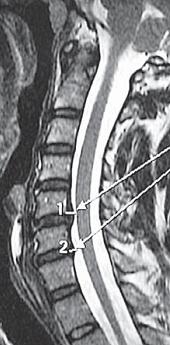

МРТ № 20

На МРТ № 20 наблюдается грыжа межпозвонкового диска шейного отдела позвоночника в сегменте CV—CVI и протрузия в сегменте CVI-CVII